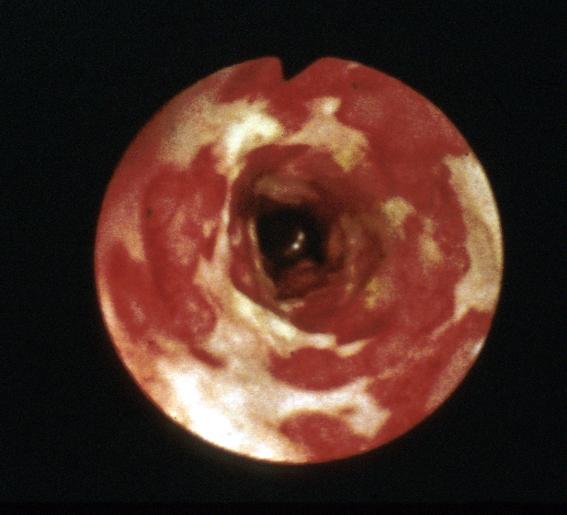

缺血性肠炎(含血栓病)

50日内X光片4次观察到其推移的狭窄型缺血性大肠炎

炎症性・溃疡性疾患/缺血性大肠炎

部位(按器官分)

大肠/横结肠

检查方法

内窥镜